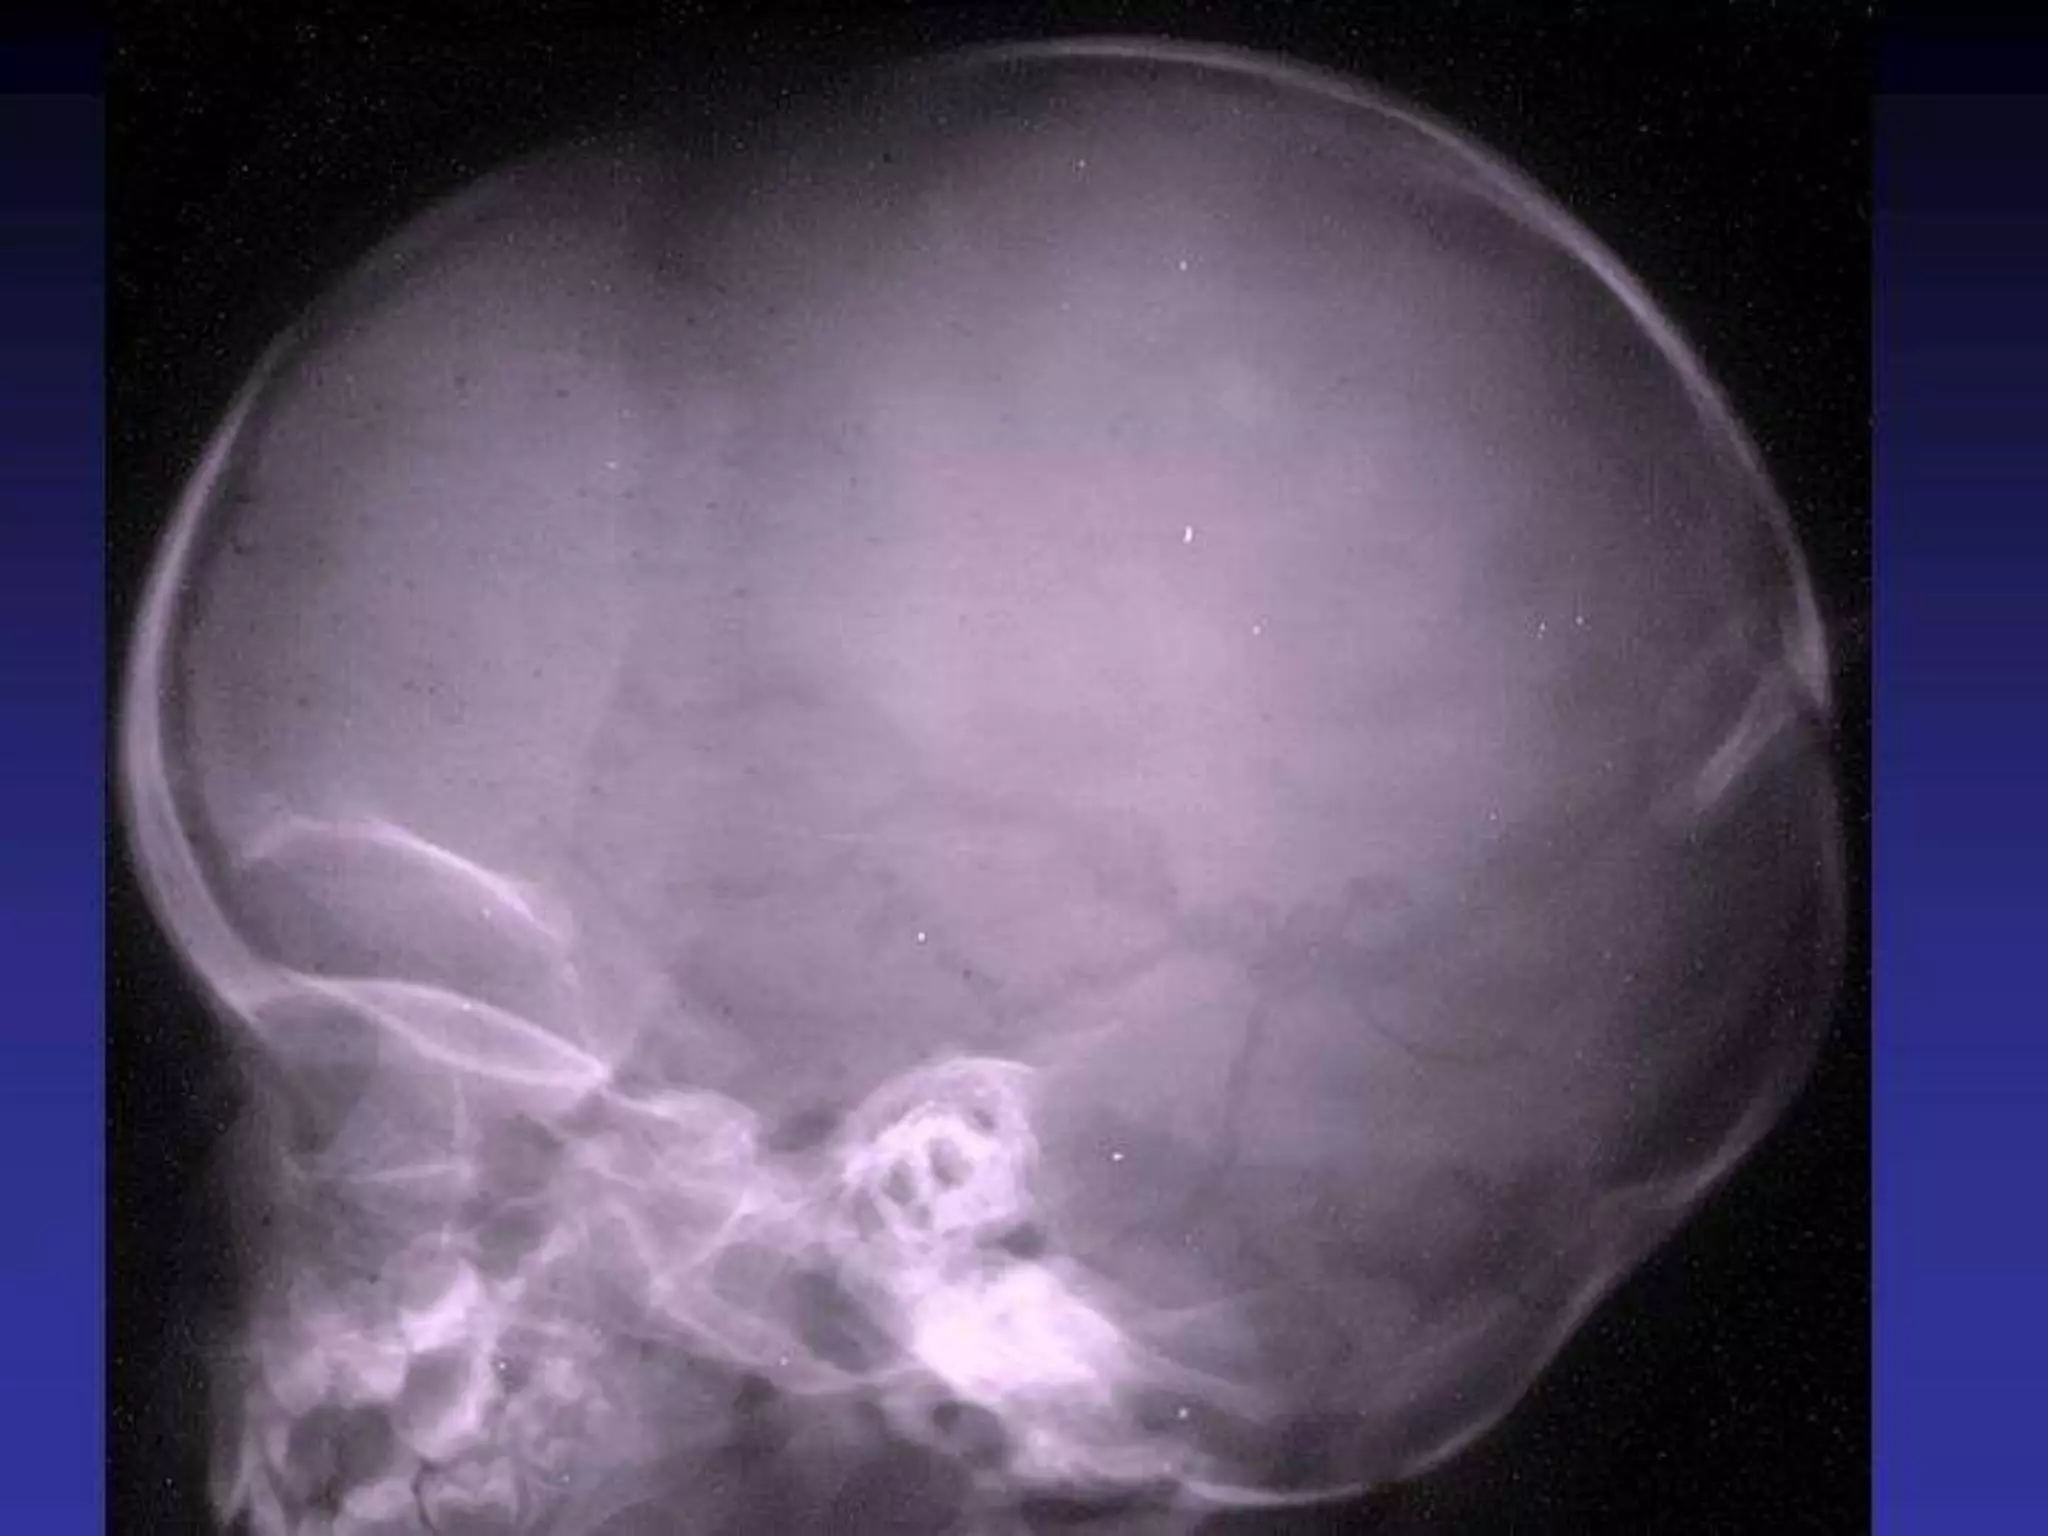

PLAIN RADIOGRAPHS

• Plain X-ray is essential modality for initial assessment

of the spine.

• Good display of bony details

• Limited value in evolution of head trauma since it

may not reflect underlying CNS damage.

• Skull radiograph helps in classification of skull

fractures and its extent and therefore further

management.

• Intracranial calcification, suture separation

Use of x ray in Neuro-radiology

• Intracranial calcification

• Raised ICT

• intracranial tumors

• Head trauma

The radiological signs of raised

intracranial pressure

• I. Suture diastasis-1ST & most important sign in

infants & children

• 2. Sellar erosion- more useful in adults,

chronic raised ICT

• 3. Pineal displacement- in adults

• 4. Increased convolutional markings(not much

informative)

Suture separation

Normal sella Sellar erosion

PLAIN RADIOGRAPHS •Plain X-ray is essential modality for initial assessment of the spine. • Good display of bony details • Limited value in evolution of head trauma since it may not reflect underlying CNS damage. • Skull radiograph helps in classification of skull fractures and its extent and therefore further management. • Intracranial calcification, suture separation

• 5.

Use of xray in Neuro-radiology • Intracranial calcification • Raised ICT • intracranial tumors • Head trauma

• 6.

The radiological signsof raised intracranial pressure • I. Suture diastasis-1ST & most important sign in infants & children • 2. Sellar erosion- more useful in adults, chronic raised ICT • 3. Pineal displacement- in adults • 4. Increased convolutional markings(not much informative)